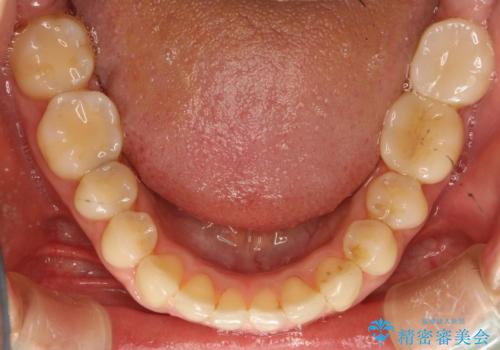

前歯のガタガタをインビザラインで目立たず矯正

- 目立たずに前歯を矯正したいとのことで来院されました。

歯と歯の間にわずかに隙間を作りスペースを確保し、インビザラインにて矯正を行うこととなりました。

前歯の微調整に少し時間がかかりましたが、整った歯並びにすることができました。